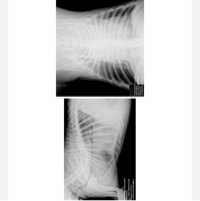

Fizemos uma série de exames com cardiologistas e descobrimos a existência de um tumor no coração do Noah, tumor este que, até agora, ainda não conseguimos descobrir se é malígno ou benigno. Este tumor, quando inflamado, acaba gerando e acumulando líquido no pericárdio, ao redor do coração do Noah, e isso faz com que o coraçãozinho dele fique apertado, funcionando com dificuldade. O coração, por estar em sofrimento, acaba não conseguindo bombear sangue o suficiente para o restante do corpo, fazendo com que os órgãos fiquem sobrecarregados e que mais líquido se acumule, se espalhando também para a região abdominal. Mesmo já tendo feito cerca de quatro drenagens (sendo três no coração e uma no pulmão, que também já acumulou líquido), este problema fica indo e vindo, nos deixando desamparadas. Ele, quando está com líquido retido, não consegue deitar direito para dormir, fica dormindo sentado, perde o apetite, fica com a respiração pesada…